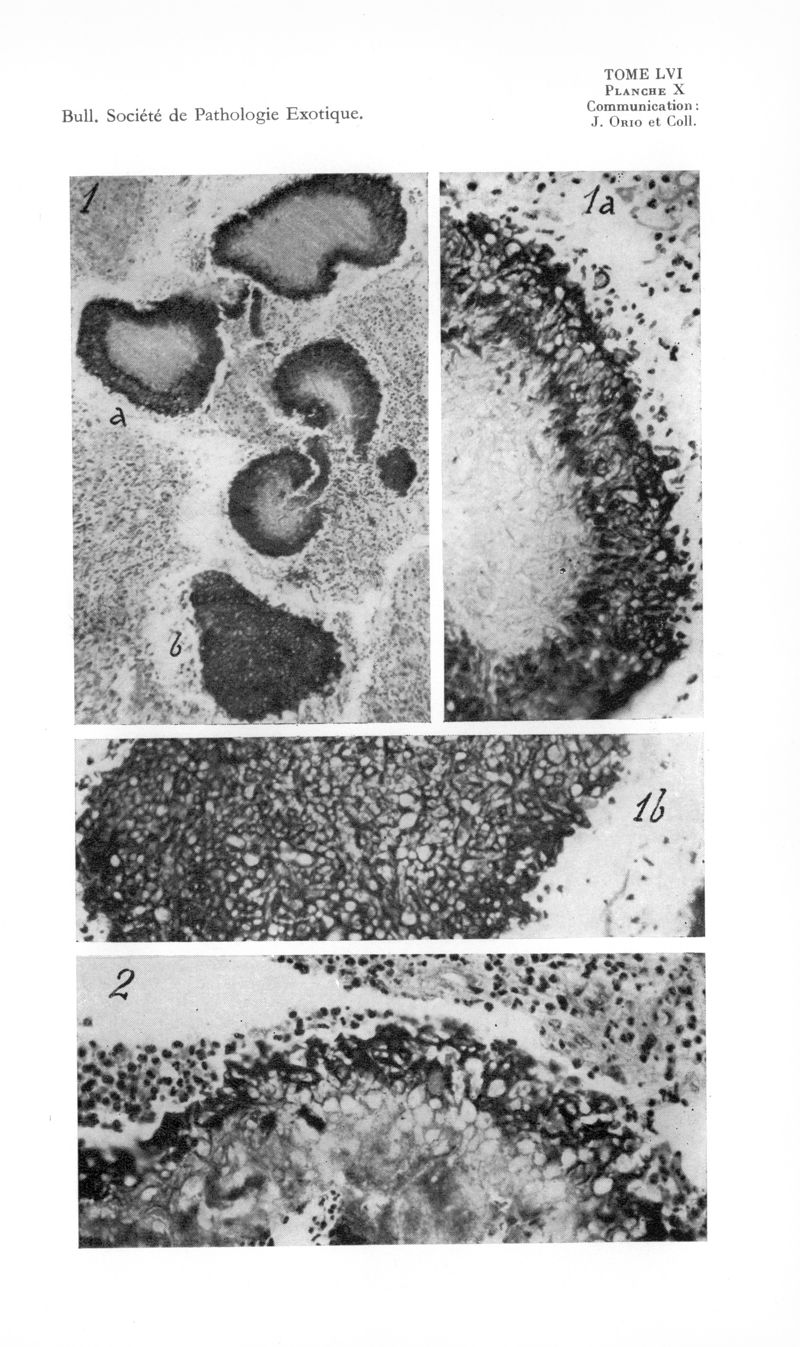

Bulletin de la Société de pathologie exotique et de ses filiales

1963, tome 56. - Paris : Masson, 1963.